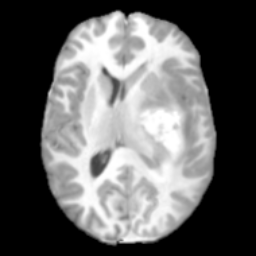

Brain MRI

We also evaluate our method on the BraTS-Reg (Baheti et al. 2021) dataset, which provides pre-operative and follow-up MRI scans for patients with diffuse glioma. The dataset includes multimodal MRI sequences (T1, T2, FLAIR, and T1 contrast-enhanced) collected longitudinally for each subject. To mitigate inter-scan variability caused by different acquisition protocols, histogram standardization (Nyul, Udupa, and Zhang 2000) is first applied to the pre-operative and follow-up T1 and T2 scans. We then perform Z-normalization, rescale the intensity to the range, and crop the scans to a resolution of . The pre-operative and follow-up scans are rigidly aligned using the SimpleITK registration framework (Yaniv et al. 2018). For experiments, 160 subjects in BraTS-Reg are split into training and testing sets with a 7:3 ratio and the central eleven slices are extracted to form a dataset with 1232 training pairs and 528 testing pairs.

4.5 Experiment Results on Brain MRI

To further demonstrate the effectiveness of TraceTrans, we additionally evaluated the model on Brain MRI dataset. The quantitative results are shown in Table 2 and TraceTrans performs best in SSIM, MAE, NMI and slightly worse than MUNIT in PSNR. Since the difference between TraceTrans and MUNIT on PSNR is less than 5% of either standard deviation, then this difference is negligible. TraceTrans shows significant SSIM improvement while matching MUNIT’s PSNR and achieving the lowest MAE, demonstrating balanced excellence in both structural and textural translation. Qualitative results are illustrated in the second row of Figure 4, the image generated by our model is visually best similar to the reference image.